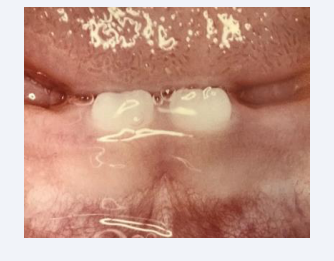

The primary dentition continues development postnatally. The first teeth to erupt in the mouth are the mandibular primary central incisors [Figure 15]. These teeth erupt about the age of 9 months and shedded when the first permanent central incisors erupt at the age of 7 years. There are specific times for eruption and shedding of the primary teeth. The primary molars are replaced by permanent premolars. The permanent molars develop independent of the primary dentition.

Figure 15 The first teeth to erupt are the primary mandibular central incisors erupting at about 9 months of age

Figure 15: The first teeth to erupt are the primary mandibular central incisors erupting at about 9 months of age.